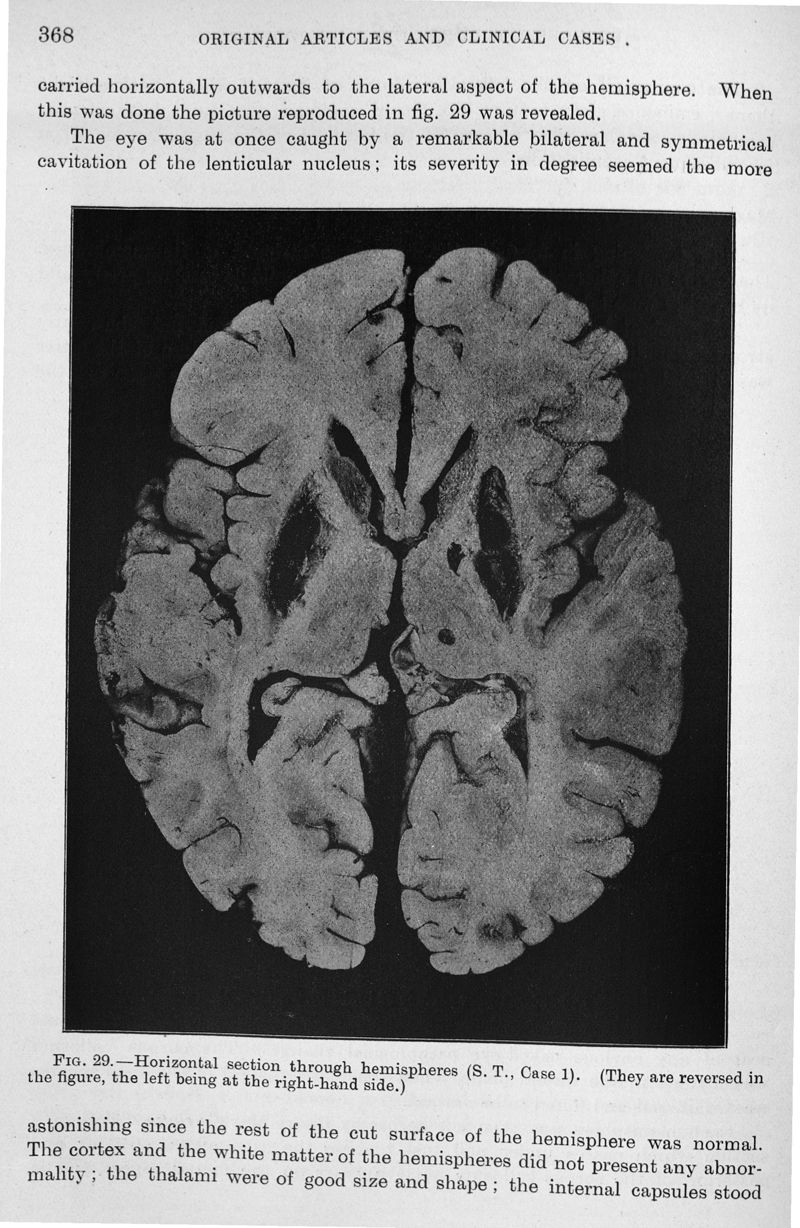

Progressive lenticular degeneration : a familial nervous disease assiociated with cirrhosis of the liver

In : Brain, 1912, Vol. 34, part IV pp. 296-509